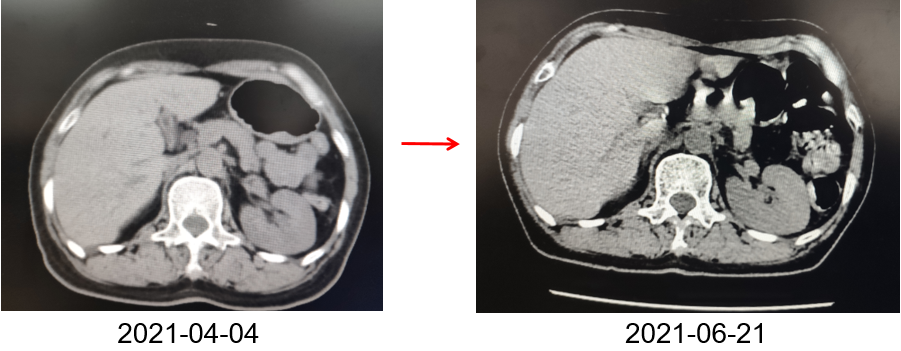

为提升肺癌前线免疫联合抗血管治疗的诊疗观念,学习与追踪肺癌领域诊疗最前沿知识,充分交流免疫/抗血管用药不良反应管理临床经验,【An例说】肺癌病例项目,征集大量临床高质量免疫联合抗血管治疗肺癌病例,并邀请全国各区域中青年及高职称医生与顶级TOP KOL互动发声!通过理念结合实践,研究结合病例,线上联动,共同促进学术由KOL/ROL向中青年医生下沉,为提升我国肺癌诊疗整体水平势在必行。免疫治疗的出现,特别是以PD-1/PD-L1为代表的免疫检查点治疗的出现,对于转移性的晚期肺癌患者而言,给患者增加了更多治疗的选择,同时,多项临床研究表明免疫治疗显著延长了患者的生存期及生活质量。为此,河北北方学院附属第一医院为您带来一例“双安疗法”用于二线治疗小细胞肺癌病例的治疗分享。 案例详情 基本情况 患者,霍xx,女,60岁。 初治时间:2020-10-16 既往史:COPD 4年,间断口服茶碱治疗,否认其他慢性病史及传染病史。否认过敏史。 个人史:无特殊 家族史:无特殊 ADL评分:90分;Khorana评分1分 入院初步检查结果 体格检查: COPD 4年,间断口服茶碱治疗,否认其他慢性病史及传染病史。否认过敏史。 个人史、婚育史、家族史无特殊。 辅助检查 血常规、肝肾功、凝血功能无明显异常。 肿瘤标志物(特异性+异常指标)。 肿瘤标志物变化趋势 NSE(神经元特异性烯醇化酶)变化趋势: NSE变化趋势 基线情况: 2020-10-16,患者无明显诱因出现咳嗽、咳痰,偶有痰中带血,伴胸闷气短4个月于我院就诊:查胸部CT:胸廓左侧塌陷,左肺上叶尖后段及下叶支气管截断,左肺下叶见软组织密度团块。右肺中叶容积小。左主支气管内见高密度影,纵隔多发肿大的淋巴结,胸膜厚,左侧少量胸膜腔积液。 浅表淋巴超声、全身骨扫描等检查提示肺外脏器未见异常。 肺部CT提示左肺占位伴阻塞性肺炎、纵隔淋巴结肿大,左侧胸腔积液。 患者遂就诊于解放军81集团军医院行支气管镜检查提示小细胞肺癌。 影像学检查 诊断结果 1.左肺小细胞肺癌(广泛期)伴胸膜转移、伴纵隔淋巴结转移 2.阻塞性肺炎 3.慢性阻塞性肺疾病 诊疗依据 (CSCO)小细胞肺癌诊疗指南2020 05治疗经过 第一阶段治疗: 胸部CT对比:较前片(2020-10-16)对比:左肺上叶复张且高密度影明显吸收;左肺占位及纵隔淋巴变化不明显,左侧胸腔积液基本吸收。 胸部CT检查对比 胸部CT对比:较前片(2020-11-26)对比:左肺占位变化不明显;纵隔部分淋巴结增大。 胸部CT检查对比 胸部CT对比:较前片(2020-12-30)对比,左肺占位明显增大,隔巴结增大,左侧胸腔新发积液,左肺上叶膨胀不全,左肺上叶新发片状高密度影。 胸部CT检查对比 胸部CT对比:较前片(2021-03-02),左肺占位性病变较前增大,纵膈肿木淋巴结较前增大。 胸部CT检查对比 胸部CT对比:较前片(2021-04-04)左肺中心型肺Ca伴左肺不张,较前增大。右肺中叶不张。纵隔多发肿大融合淋巴结,部分包绕上腔静脉,较前增大。心包少量积液、主肺动脉干增粗。左侧胸腔积液(±)。 胸部CT检查对比 头颅CT对比:2021-06-21头颅CT:考虑左枕叶、右颞叶转移瘤。尾状叶头密度增高。 头颅CT检查对比 腹部CT:较前片(2021-04-04)左肾上腺增粗,考虑转移瘤? 腹部CT检查对比 第二阶段治疗:免疫+安罗替尼。ADL评分:70分;Khorana评分3分。 胸部CT对比:对比前片(2021-06-21),左肺占位减小,纵隔部分淋巴结减小,胸腔积液吸收。 胸部CT检查对比 头颅CT对比:对比前片(2021-06-21):颅内占位变化不著。 头颅CT检查对比 胸部CT对比:对比前片(2021-07-27):左肺占位减小,纵隔部分淋巴结减小;左肺上叶片状高密度影略显吸收。 胸部CT检查对比 胸部CT对比:对比前片(2021-8-23):左肺占位及纵隔淋巴结有所减小。 胸部CT检查对比 胸部CT对比:对比前片(2021-10-29):左肺占位及纵隔淋巴结变化不著。 胸部CT检查对比 头颅CT对比:较前片(2021-07-01)对比:左枕叶、右颞叶占位明显减小。 头颅CT检查对比 胸部CT对比:对比前片(2021-11-30):左肺占位及纵隔淋巴结变化不著,腹部较前变化不著。 胸部CT检查对比 目前情况:患者神清,精神尚可,无咳嗽咳痰,偶有喘憋气短,饮食睡眠尚可,二便正常。 面部及双手皮疹样改变。 目前诊断: 1. 左肺小细胞肺癌(广泛期)伴胸膜转移、伴纵隔淋巴结转移、伴脑转移、伴肾上腺转移 2. 慢性阻塞性肺疾病 3. 下肢静脉血栓形成 4. 低钠血症 ADL评分:80分;Khorana评分2分 06病程回顾 专家点评 该病例,女性,无吸烟史,既往自2014年开始反复因咳嗽、咳痰、咯血于我院门诊或住院治疗,诊断为右中叶、双下肺基底段支气管扩张伴感染。2020年10月再次因咳嗽、咳痰、咯血行肺CT检查,检查结果示:支气管扩张、左下肺占位。后经支气管镜检查左下肺癌,病理为小细胞癌。结合肺CT:纵隔淋巴结肿大,左侧胸腔积液;临床诊断为:原发性支气管肺癌(左下广泛期小细胞肺癌)。PS评分1分,依据2020年CSCO小细胞肺癌指南Ⅰ级推荐选择化疗+免疫治疗,化疗方案:CE/EP,IC/IP,免疫治疗:atezolizumab。本病例中,患者因经济条件所限,未使用atezolizumab,化疗采用CE\EP\ZP一线及二线LE(共计7疗程),肺部病灶增大,左肺完全不张,脑转移,肾上腺转移,PS评分3分。再次依据CSCO指南,行颅脑放疗,采用PD-1(卡瑞丽珠单抗)+EP+安罗替尼(口服小分子多靶点抗血管生成药物)2个疗程后,肺部病灶明显缩小,颅内病灶消失,评效为PR;后因卡瑞丽珠单抗副作用:反应性皮肤毛细血管增生症(RCCEP)及手部皮肤皲裂,改换为派安普利单抗+EP+安罗替尼治疗,直至目前。左肺完全复张,病情明显改善,PS评分降至2分。 该患者全程治疗过程分析,单纯化疗疗效不显著,PD-1联合抗血管生成靶向药物后,使得患者病情控制,生存带来了希望。“双安”治疗方案副作用小,对PS评分高的患者也适用。派安普利单抗是唯一采用IgG1亚型且经FC段改造的新型PD-1单抗,副作用较国产其他IgG4亚型 PD-I更小;安罗替尼为口服小分子多靶点络氨酸酶抑制剂,靶点更加全面,疗效更优。采用“双安”治疗广泛期小细胞肺癌,本例虽为个例,但为临床医生提供了可践行的治疗方向,也期待着更多临床研究数据的公布,为小细胞肺癌的治疗提供强有力的治疗依据。 病例分享 王布 教授 河北北方学院附属第一医院呼吸科副主任医师,医学硕士 河北省中西医结合睡眠专业会委员 张家口市抗癌协会肺癌专业委员会委员 世界中医药学会联合会整合肿瘤专业委员会委员 在《Translational Cancer Research》、《Journal of biological regulators &homeostaticagents》、《中国临床药理学》、《中华结核与呼吸杂志》等杂志上发表学术论文10余篇,其中《川芎嗪联合顺铂影响Lewis肺癌小鼠移植瘤生长及微血管生成的研究》论文在2015年中国药学大会暨第十五届中国药师周上报告交流 荣获河北省科技进步三等奖1项,河北省医学会科技奖一等奖1项 目前以第一主研人主持河北省科技厅课题1项,市厅级课题2项 以第二主研人主持张家口市财政厅支持课题1项;河北省政府资助专科能力建设和专科带头人培养课题1项 获“河北省抗击新冠肺炎先进个人”、“河北省优秀共产党员”、“河北省冀青之星”、张家口市“最美科技工作者”,“张家口市抗击新冠肺炎先进个人”、“张家口市优秀共产党员”等荣誉称号。 专家点评 支学军 教授 河北北方附属第一医院主任医师 教授,河北北方学院硕士研究生导师 任河北省医学会内科学分会委员 张家口市医学会呼吸分会常务委员兼秘书 张家口市抗癌协会理事会理事 张家口市抗癌协会肿瘤临床化疗专业委员会常务委员 张家口市抗癌协会抗癌药物专业委员会常务委员等职务 从事呼吸科工作30余年,擅长肺部感染性疾病、肺癌、肺结核等疾病的诊治。